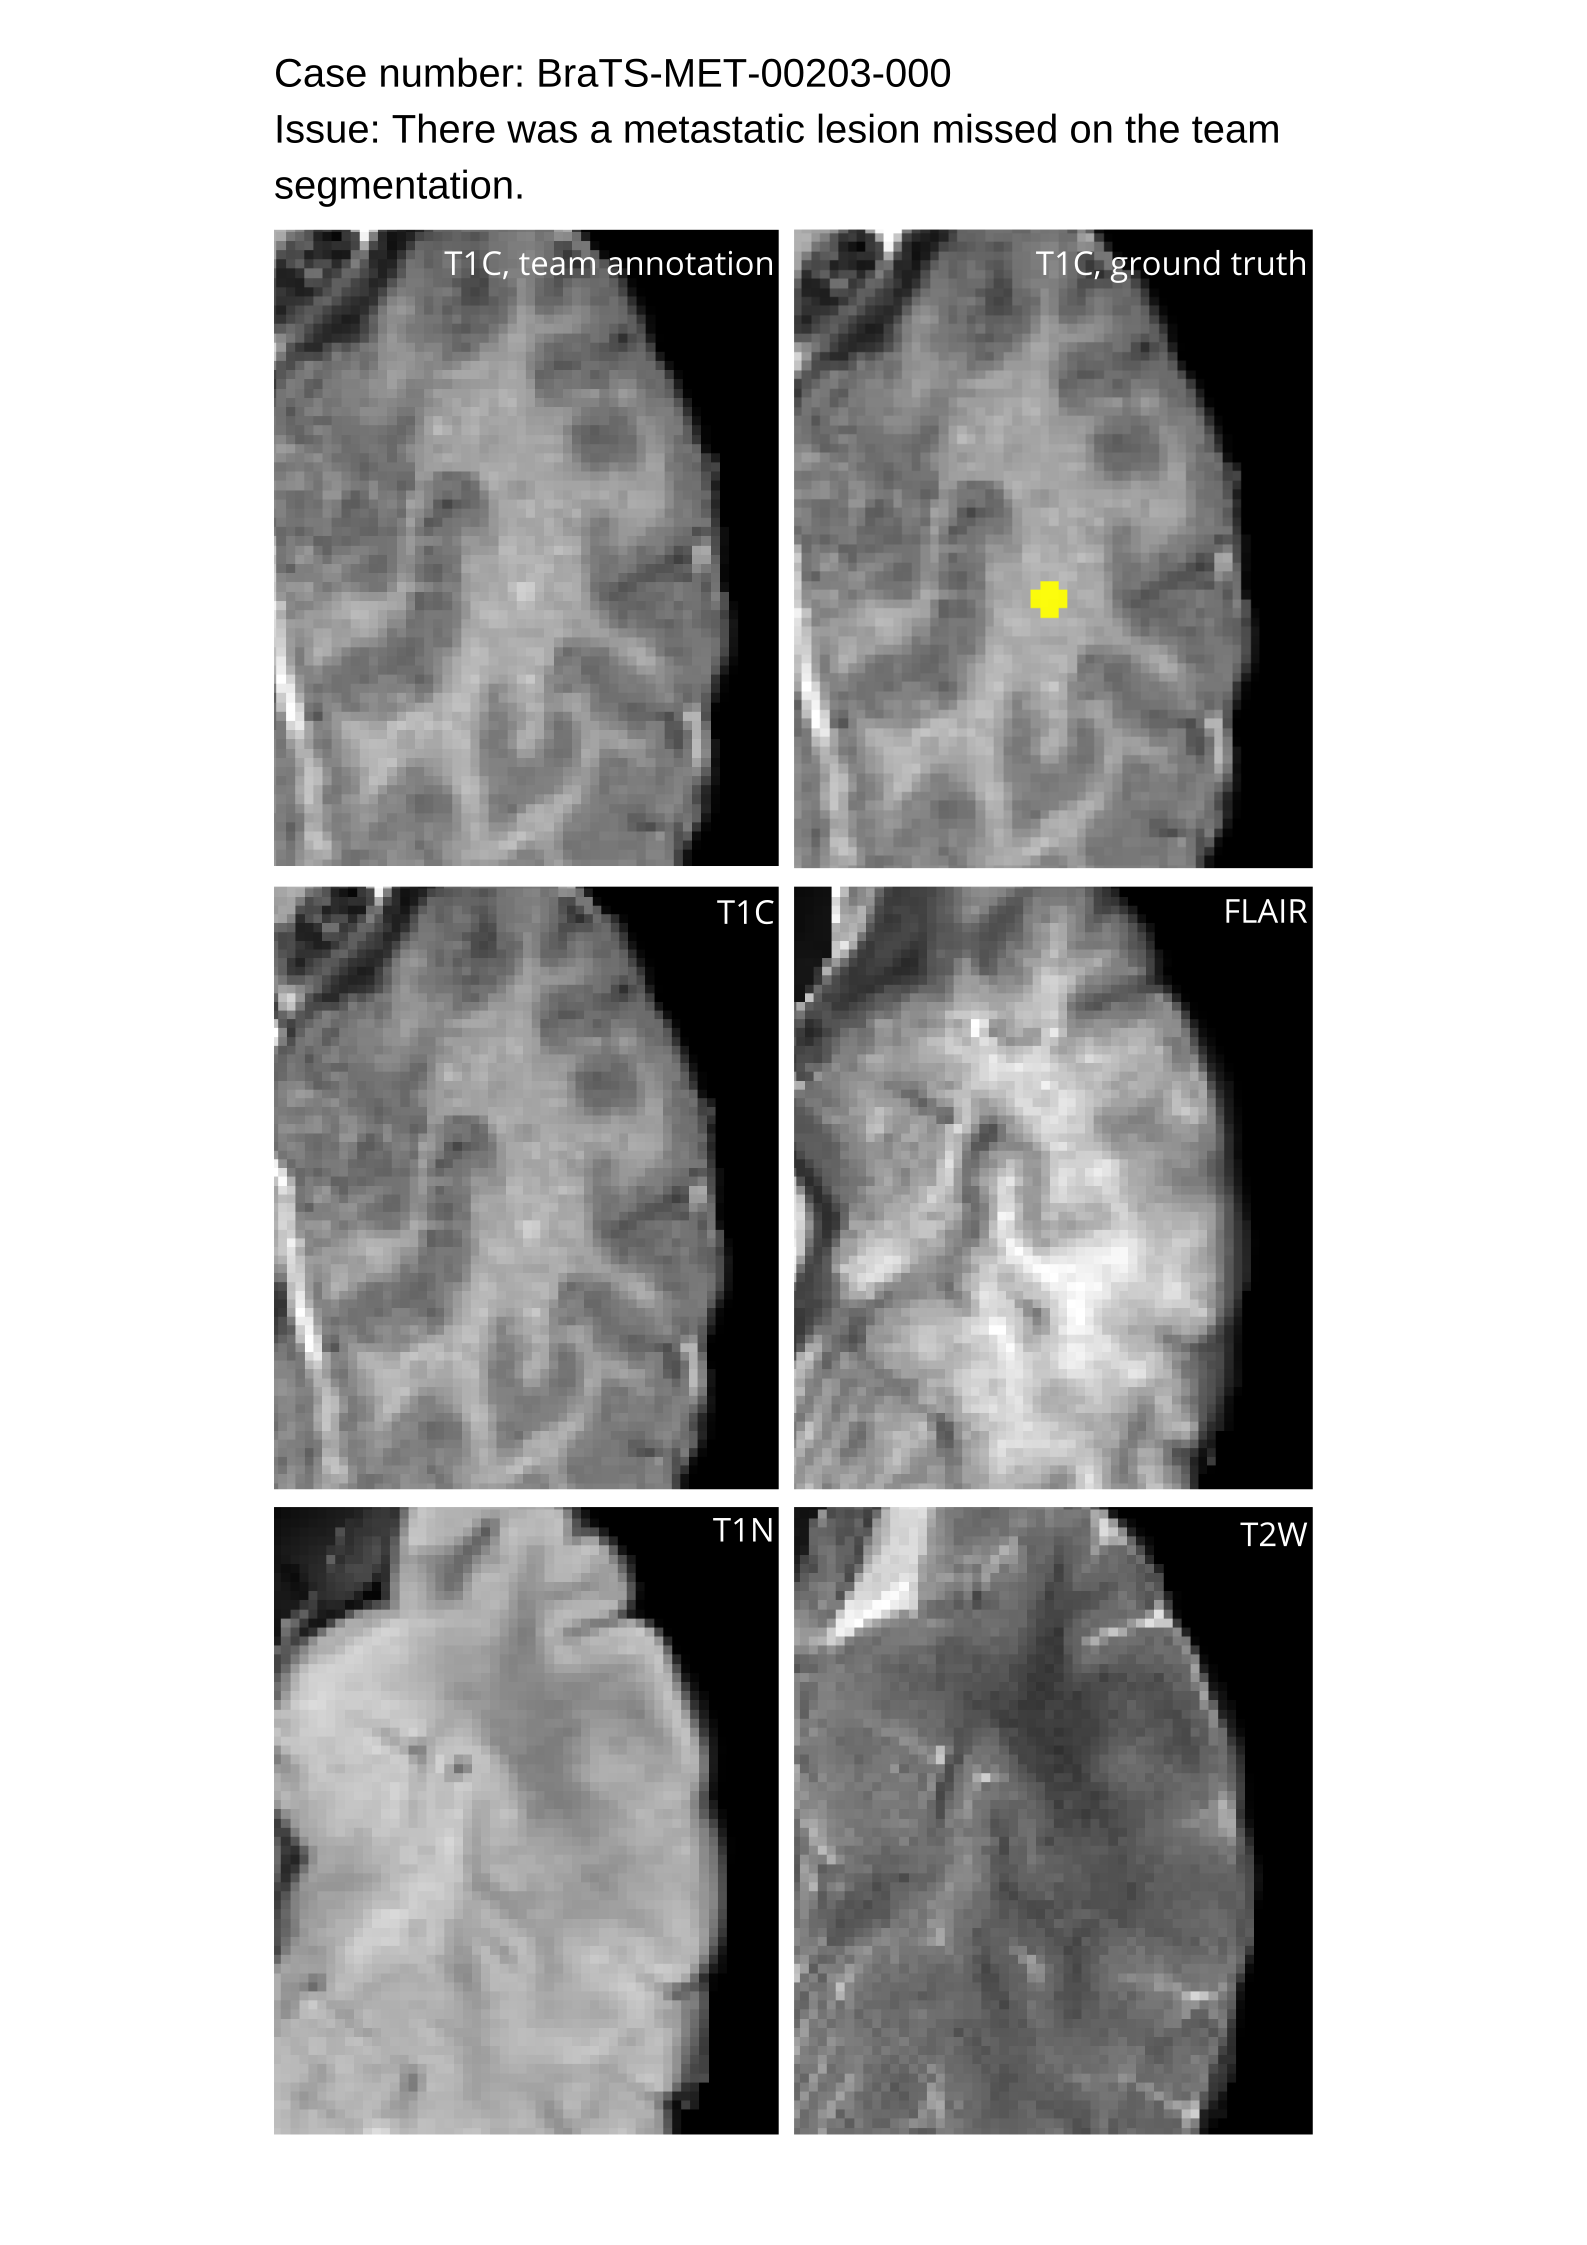

4.9 Common Errors of Automated Segmentations

Based on observations from previous BraTS challenges, common errors in automated segmentations were identified. The most typical errors in the current challenge included:

1. 1.

Automated algorithms missing small metastases. Enhancing metastasis was fused using the minority voting algorithm to aggregate all enhancing tumor voxels identified by the three algorithms. However, many small metastases were missed and were manually segmented by neuroradiology attendings.

2. 2.

Segmentation of white matter changes from microvascular disease. Peritumoral edema segmentations were checked by neuroradiology attendings and modified.

3. 3.

The segmentation of non-enhancing lesions that have intrinsic T1 hyperintensity. Voxels with intrinsic T1 hyperintensity were manually removed from ET segmentations.

These insights led to specific adjustments in the annotation process to enhance accuracy.